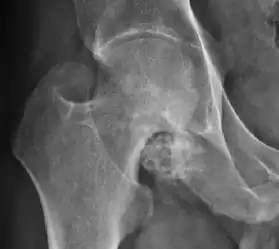

Synovial chondromatosis can be confidently diagnosed by X-ray when calcified cartilaginous chondromas are seen. However, other synovial proliferative processes, such as pigmented villonodular synovitis, require MRI for accurate diagnosis, although noncalcified synovitis can be suspected in radiographs by indirect signs, such as soft tissue swelling and/or erosions in the femoral head, femoral neck, or acetabulum (Figure 7).[1]

Figure 7:

-

Axial CT image of pigmented villonodular synovitis eroding the posterior cortex of the femoral neck.[1] -

Sagittal T2* gradient echo image showing a posterior soft tissue mass with hypointense areas secondary to hemosiderin deposition.[1] -

X-ray of synovial chondromatosis.[1] -

CT of synovial chondromatosis.[1]

In synovial proliferative disorders, MRI demonstrates synovial hypertrophy. In the case of PVNS, characteristic foci of low signal intensity related to hemosiderin deposition are better seen on gradient echo T2* images (Figure 7). In the case of synovial osteochondromatosis, the synovial hypertrophy is accompanied by intermediate signal cartilaginous loose bodies and/or low signal calcified loose bodies.[1]